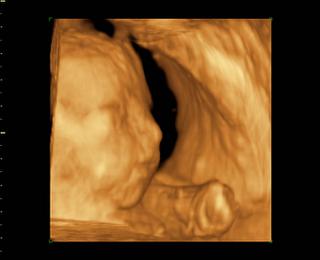

@bv_alexandra 3Dčko je skôr pre potešenie, morfologický UV je na diagnostiku, vidno na ňom orgány a kosti bábätka, vidno chlopne srdiečka, je možné zmerať dĺžku kostí a tak podobne, len pre porovnanie, už som to sem dávala aj predtým a písala som o tom, pridávam ti fotky z môjho prvého tehu, tie "farebné" sú z 3Dčka tam je krásne vidieť bábätko, tváričku, črty tváre, je vidieť na koho sa podobá, ako vyzerá, na morfologickom, to je ten čiernobiely vidieť bábo "zvnútra" aby sa potvrdilo že je úplne zdravé a nemá žiadne vývojové vady, podľa dĺžky kostí ti tam aj spresnia termín pôrodu.